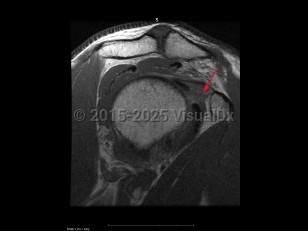

Classic history and presentation: Adhesive capsulitis typically follows a course of 3 phases. First (2-9 months), there is an insidious onset of pain that eventually becomes severe and disabling. The pain tends to be worse at night and stiffness gradually onsets. Second (4-12 months) is the contracture phase, which is characterized by stiffness and progressive loss of motion that interferes with activities of daily living. Pain typically improves in this phase. Third (5-24 months) is the recovery or "thawing" phase in which the symptoms gradually alleviate and there is an improvement in range of motion (ROM).

Grade / classification system: Adhesive capsulitis can be classified as primary, which is idiopathic, and secondary, which is onset due to trauma or immobilization.